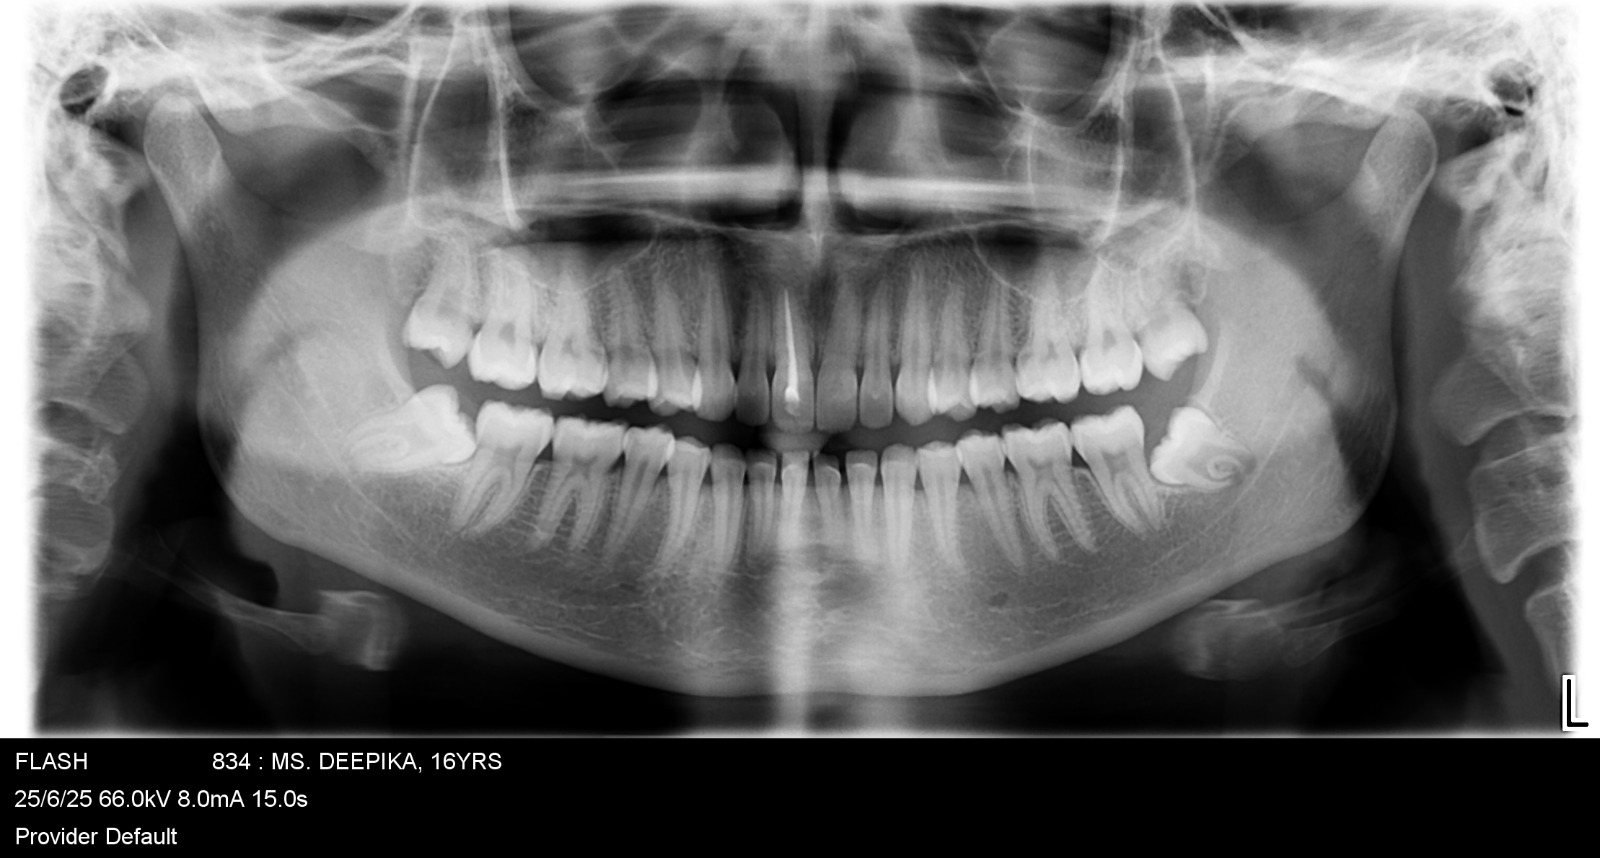

Images Of Dental Treatment Servcies Done At Our Hospital